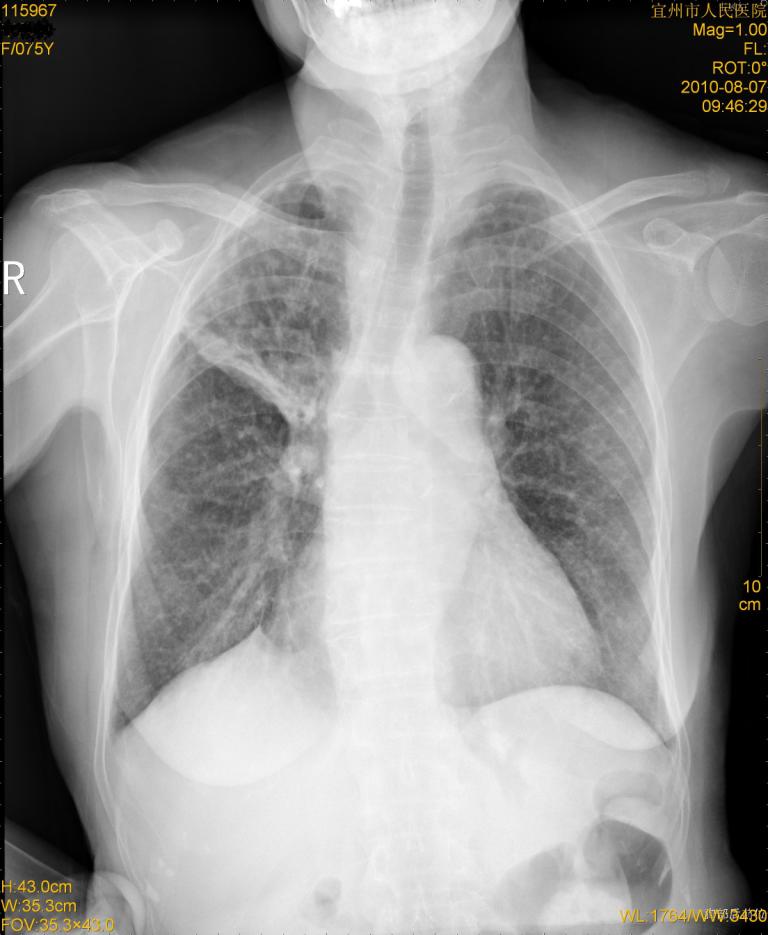

标题: CT28313:两肺弥漫性病变 [打印本页]

标题: CT28313:两肺弥漫性病变

女,75岁,患者反复头昏乏力面色苍白3年,再发10天入院。临床贫血查因。

双肺间质增生并右肺上叶炎性改变,不除外右肺上叶结核病肺内播散

考虑慢支伴右上肺慢性感染可能性大,建议结合临床排外尘肺可能。

考虑右肺上叶炎症合并双肺结核可能性大,建议上传纵隔窗ct图片。

双肺结核可能性大

右肺上叶继发性肺结核伴肺内血型播散!

考虑右肺上叶继发性肺结核伴两肺播散。